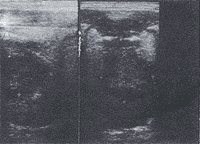

原发性舌癌的二维超声显像特征 本组结果显示原发性舌癌超声显像表现依瘤体大小不同及病变类型不同而异。瘤体小者表现为境界清晰、内部回声尚均匀的低回声结节(图1);瘤体大者(T2期以后)多表现为边缘不光滑、形态欠规则、回声欠均匀的低回声团块。伴瘤体跨越舌中线者,则声像图上舌中隔线连续中断或消失(图2左);溃疡型者,声像图上溃疡面呈高或强回声光点、光斑(图2右);浸润型病灶侵及口底舌外肌者声像图上低回声病灶超出主舌块区(图3),受侵处口底、舌外肌声像失常,舌活动度亦受限。

病灶为回声不均匀低回声结节,侵入口底舌外肌,舌中线消失

图3 舌游离部鳞癌 左为正中纵切面,右为横切面